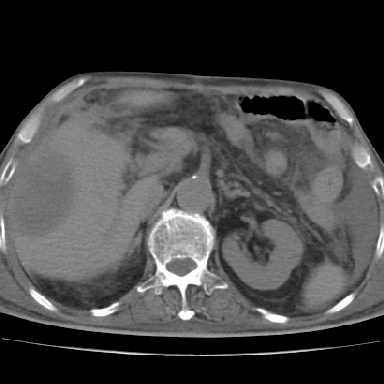

以下是引用chry3在2006-12-4 21:05:00的发言:[br]应该往上扫几层,我考虑膈下脓肿。[br]大家考虑:胃部手术怎会造成肝内脓肿,隔下脓肿到是会造成的

以下是引用qian在2006-12-4 19:11:00的发言:[br]胸腔和腹腔内均见有液性影,肝上极包膜下有一较大椭圆形低密度影,密度均匀,边缘清晰,结合病史考虑术后肝脓肿并胸腹腔积液。

以下是引用dyqct在2006-12-4 19:54:00的发言:[br]考虑:1、肝包膜下脓肿;[br] 2、少量腹水;[br] 3、右侧少量胸膜腔积液。